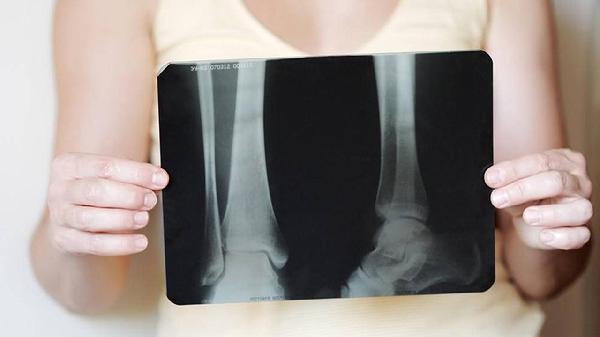

跗骨联合的临床表现有哪些

跗骨联合主要表现为足部疼痛、活动受限、步态异常等症状,可能由先天性发育异常或后天创伤等因素引起。跗骨联合是相邻跗骨间异常连接的病理状态,常见类型包括跟距联合、距舟联合等。